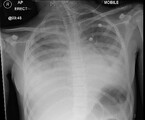

Aus diesem Grund erfolgt am 7. Krankheitstag die Verlegung der Patientin in ein kindernephrologisches Zentrum. Zu diesem Zeitpunkt besteht eine Anurie. Der Hb-Wert beträgt jetzt 8,6 g/dl, im Blutausstrich finden sich Fragmentozyten, die Thrombozyten betragen 44.000/µl. Angestiegen sind die Leukozyten auf 71.700/µl, das Kreatinin auf 5,6 mg/dl, der Harnstoff auf 168 mg/dl und das CRP auf 116 mg/dl. Nach wie vor bestehen eine leichte Hyponatriämie und eine metabolische Azidose. Im Röntgen-Thorax sind ein beidseitiger Pleuraerguss und ein geringes Lungenödem erkennbar (Abb. 1).

Am Folgetag kommt es zur kardiorespiratorischen Dekompensation (Tachypnoe, Tachykardie, Sättigungsabfall) des Kindes mit zunehmender Enzephalopathie, sodass die Verlegung auf die Intensivstation erfolgt. Bei ausgeprägtem Lungenödem und Pleuraergüssen (Abb. 3) wird mit der Hämofiltration begonnen. In der Echokardiographie ist eine deutlich eingeschränkte systolische Funktion beider Ventrikel erkennbar, das Troponin T ist mit 3329 ng/l (0 – 13 ng/l) stark erhöht. Es folgt eine einwöchige Katecholamin-Pflichtigkeit.